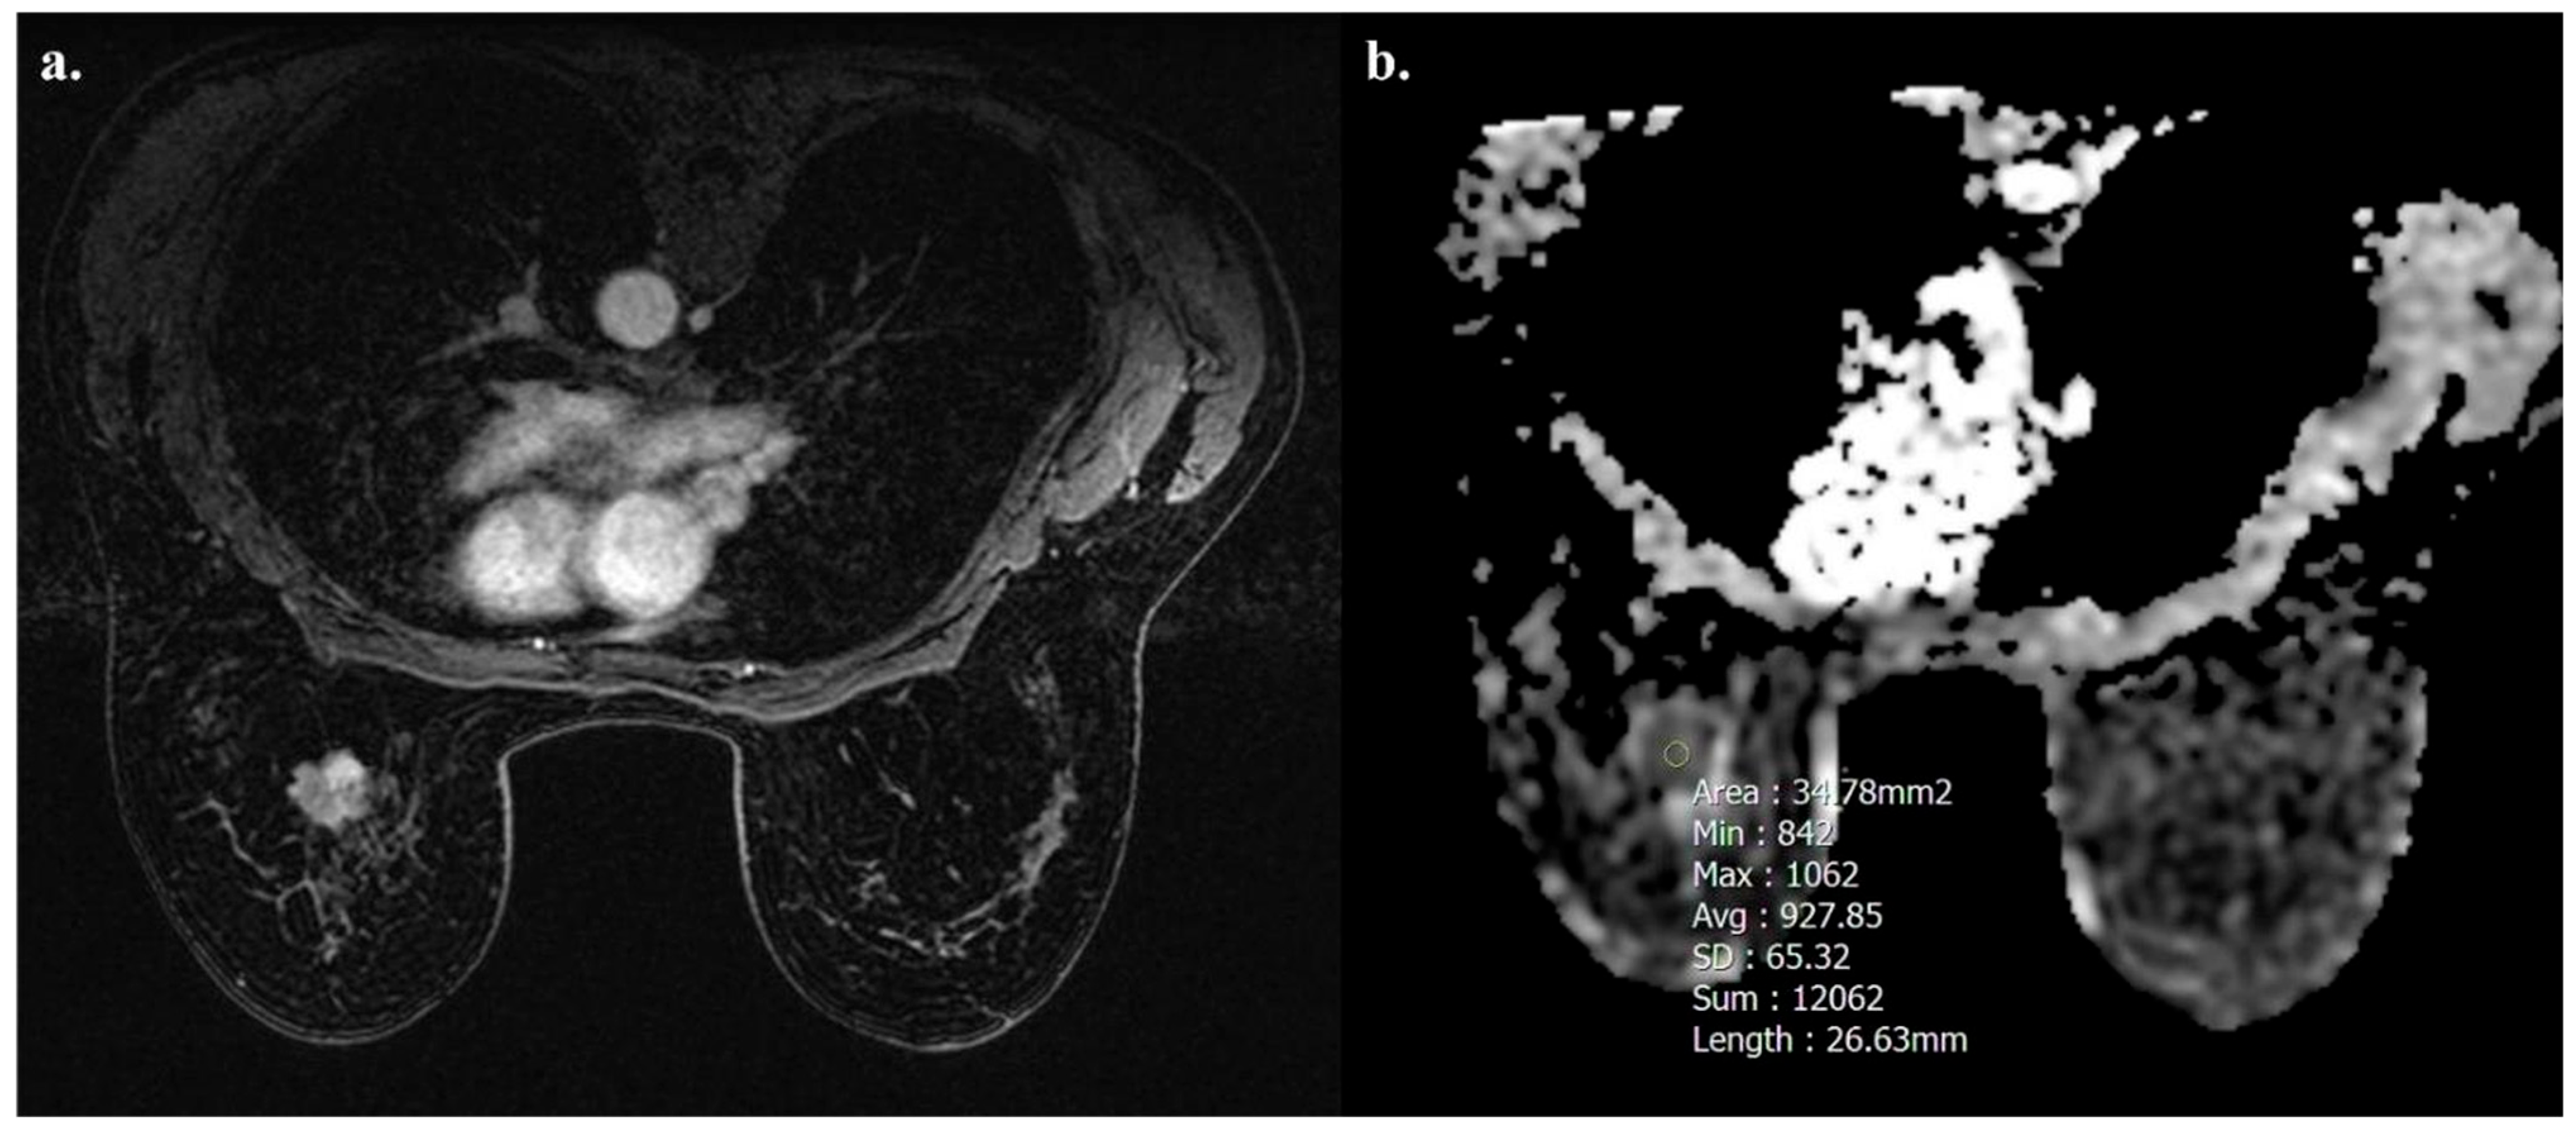

Tumors with high TIL levels also showed more frequently homogeneous enhancement compared to those with low TIL levels (31/54 [57.4%] vs. 17/91 [18.7%], p < 0.001) (Figure 3 and Figure 4).

Figure 3.

A 32-year-old woman with NST BC subtype Luminal B with high TIL levels (35%) in the right breast. Axial T1-weighted contrast-enhanced MR image shows homogeneously enhanced mass (a), and hypointensity on ADC map (0.795 × 10−3 mm2 s−1), as showed by the circle (b).